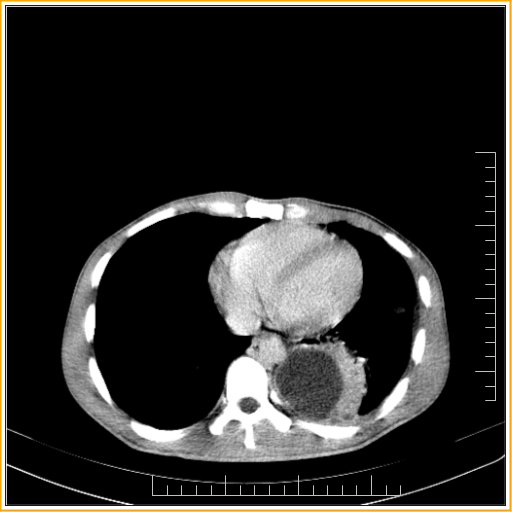

Appendicitis complicated with Subphrenic Abscess

Right subphrenic collection is noted with cresenctric shape and thick enhancing peripheral wall suggesting relatively walled off subphrenic collection. Appendix region appears thickened with surrounding periappendiceal stranding and thickening of anterior renal & lateroconal fascia. Cecal wall appears thickened.These findings possibly suggest appendicitis sequale and loculated subphrenic collection with associated pleural collection. Pus under a patient's diaphragm has usually spread there from somewhere else in his abdomen. A subphrenic abscess may be secondary to: (1) Peritonitis, either local or general, following a perforated peptic or a typhoid ulcer , or appendicitis or PID or infection following Caesarean section (2) An injury which has ruptured a hollow viscus and contaminated his peritoneal cavity (3) A laparotomy during which his peritoneal cavity was contaminated. (4) A ruptured amoebic liver abscess